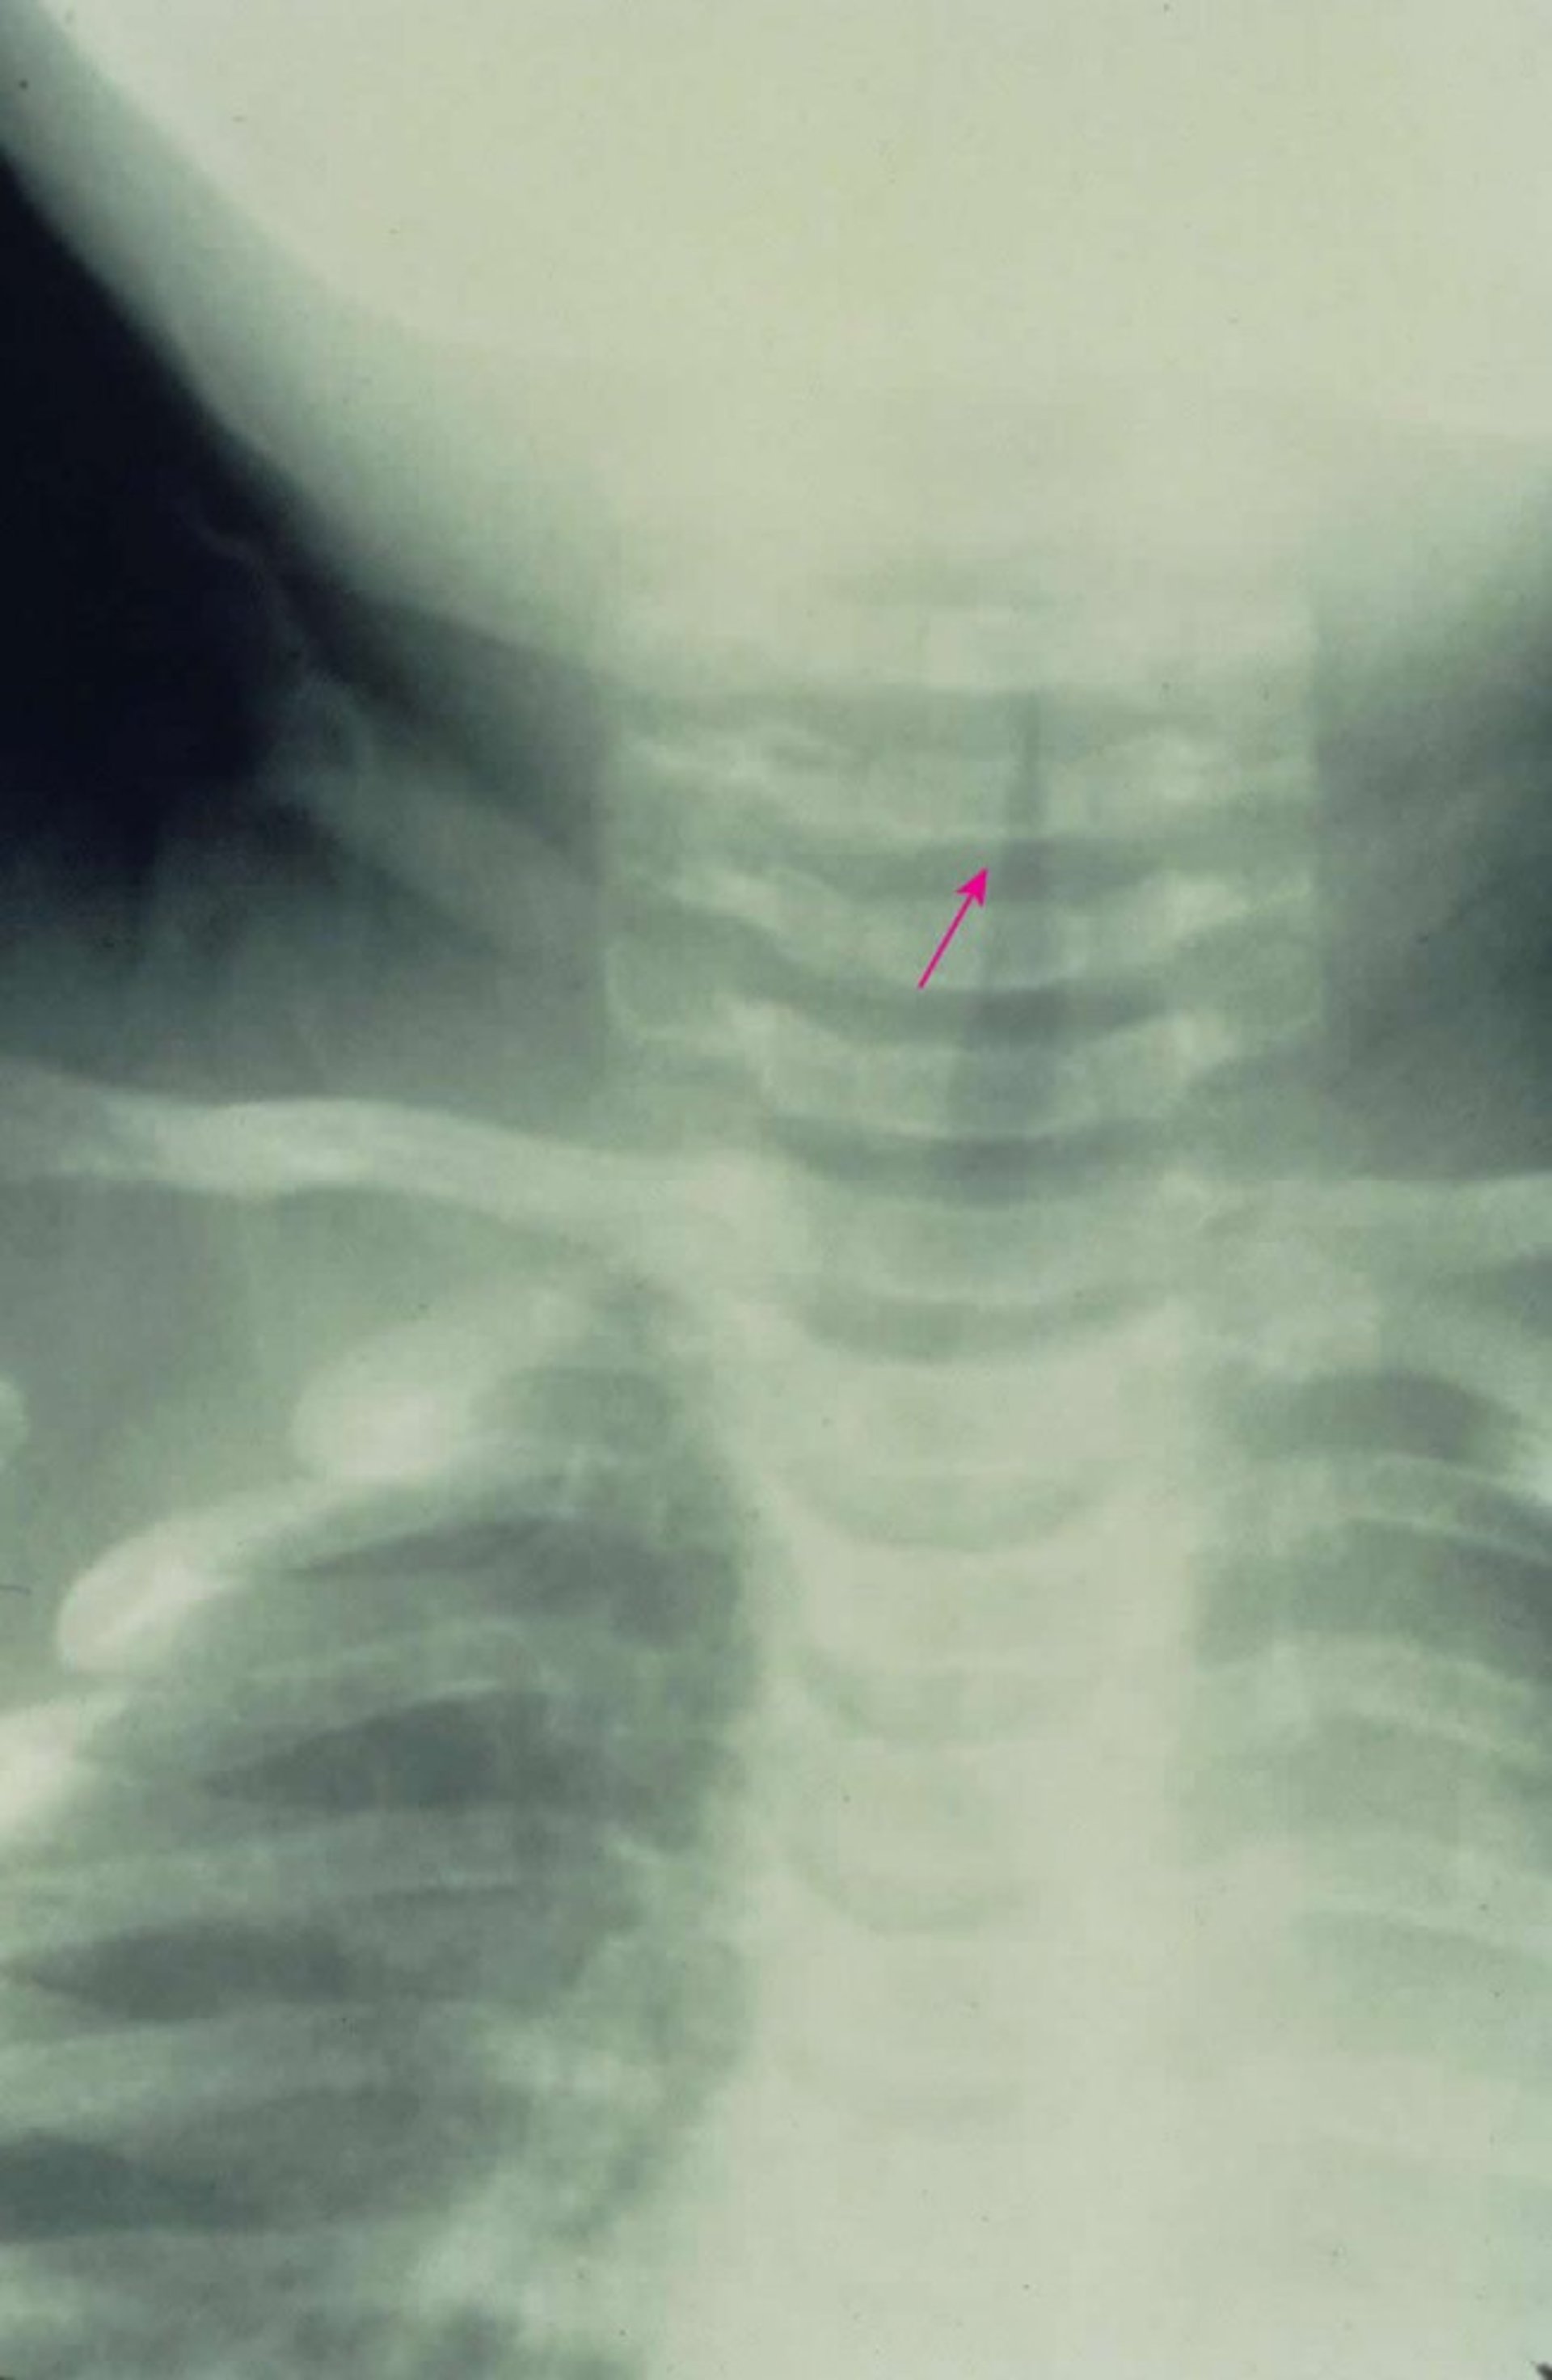

Subglottic Croup

This anterior-posterior x-ray shows characteristic subglottic narrowing of the airway (steeple sign [arrow]) caused by croup.

Image provided by Clarence T. Sasaki, MD.